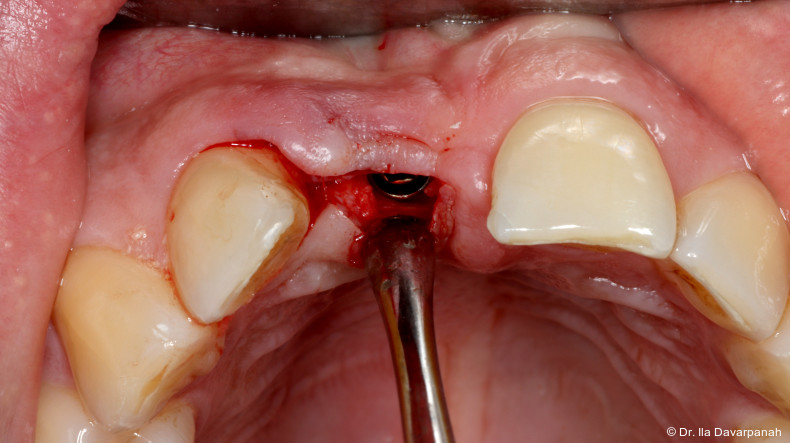

Therapie und Reimplantation

Nach Entfernung des frakturierten Implantatkörpers erfolgte eine erneute Sofortimplantation mit einem alternativen Implantatdesign. Begleitend wurden Maßnahmen zur Stabilisierung von Hart- und Weichgewebe durchgeführt.

Die postoperativen Verlaufskontrollen zeigten stabile periimplantäre Verhältnisse ohne weitere Komplikationen. Die Osseointegration sowie die Weichgewebesituation stellten sich unauffällig dar.